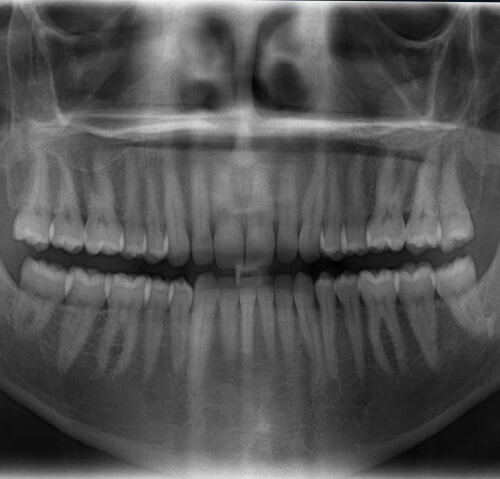

1. 치주염(치주질환, 풍치)

풍치 혹은 치주질환이라고도 부르는 치주염은

치아주변에 염증이 생겨서 붓거나 시리고

통증이 동반되는 증상을 나타내는 질환입니다.

일반적으로 치은염으로부터 시작되고 잇몸이

부었을 때는 해당 질환의 상태가 중증인

단계이기 때문에 그 심각성을 인지하여야

합니다.

특징으로는 잇몸 전반적으로 염증이 생기고,

붓기가 발생할 수 있고, 양치질할 때 잇몸에서

피가 자주 날 수도 있습니다.